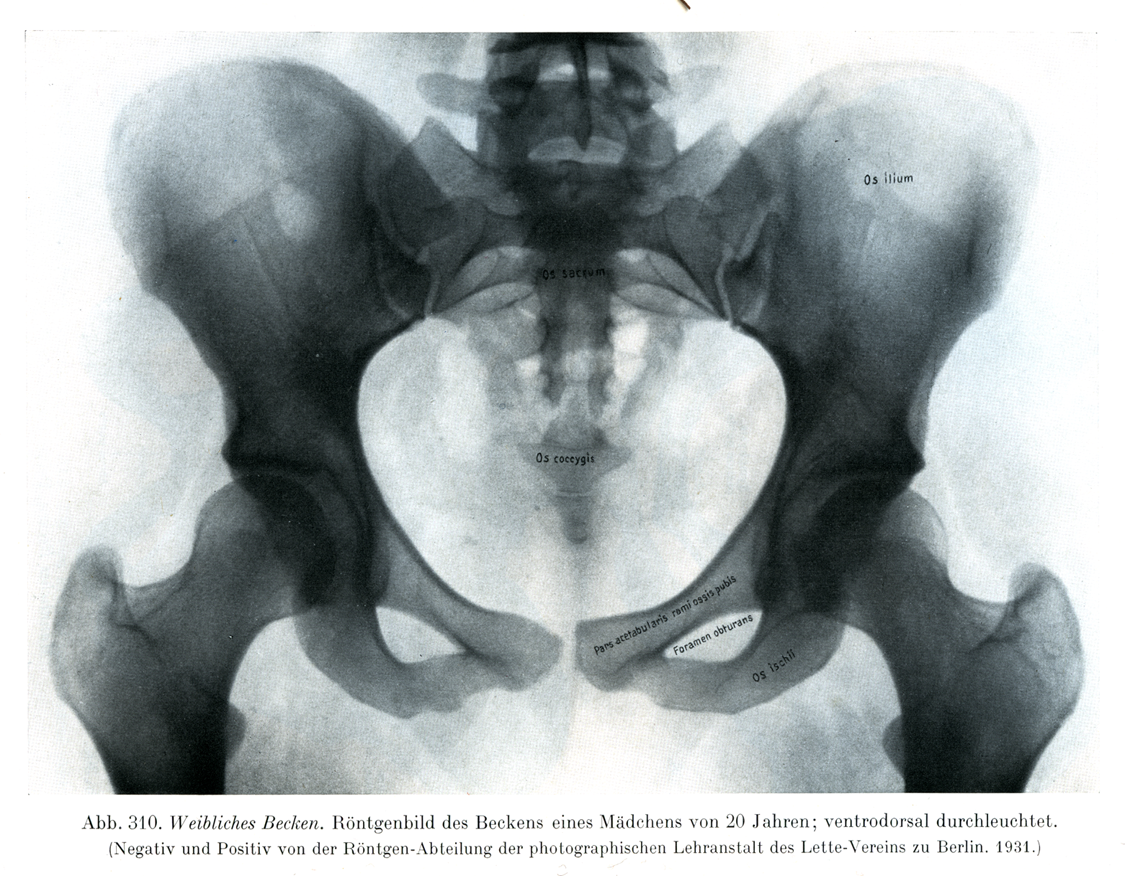

図310

女の骨盤

20才の少女の骨盤のレントゲン写真, 腹背照射.